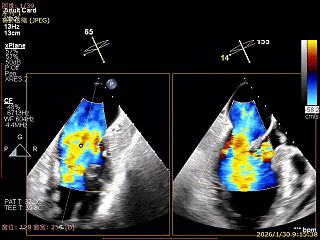

送入第2枚XTR在左房调整轨迹及Orientation

进入瓣下重新确认Orientation及位置

捕捞瓣叶,确定瓣叶瓣尖稳定插入夹臂后,Gripper Down

关紧后,前后叶受限明显

3D Enface下组织桥稳定无反流

夹子释放后,反流基本消失

LVOT切面可见主瓣二尖瓣术后反流基本消失

植入两枚夹子后二尖瓣平均跨瓣压差2mmHg